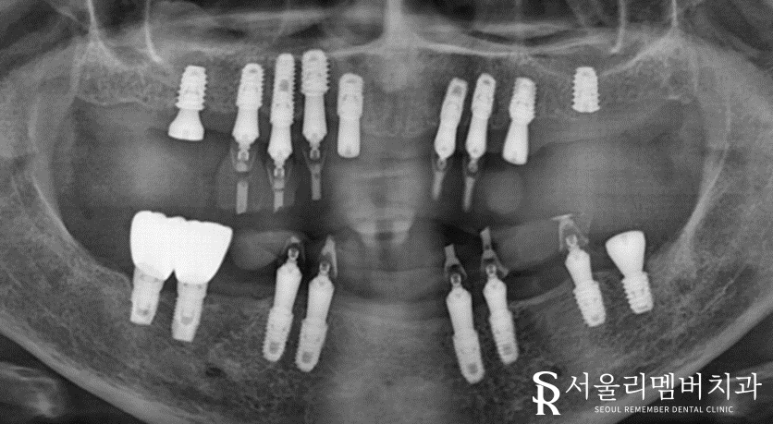

식립 할 개수가 많기 때문에 좀 더 정확한 분석이 필요했는데요.

주변 조직과의 관계, 위치, 형태를 확인한 뒤에 본격적인 치료 진행했습니다.

정확한 위치에 단단하게 심어주었습니다.

구강 상태가 좋지 않았던 거에 비해

다행히 골융합은 그리 나쁜 편이 아니네요.

별문제 없이 임플란트를 심을 수 있었습니다.